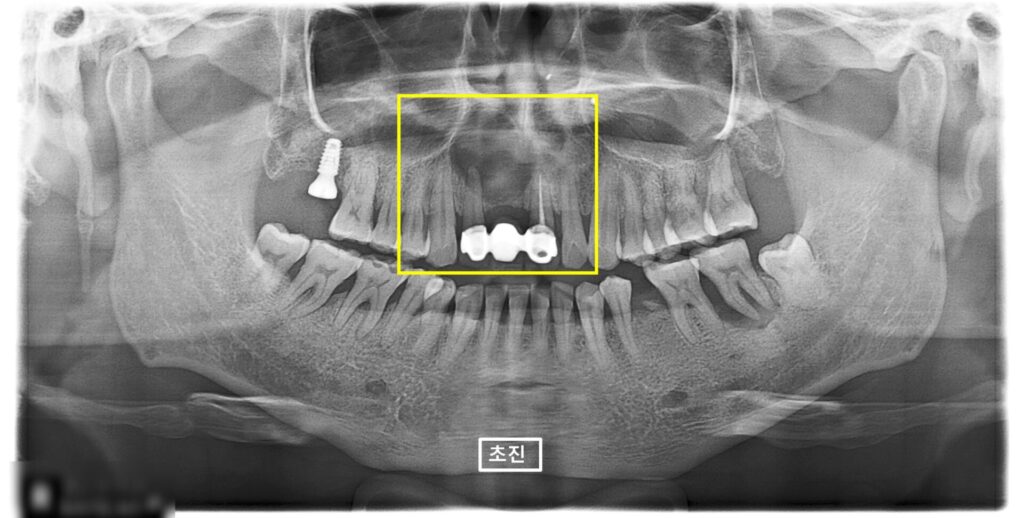

24.04.18 (초진) – 43y 김OO님

” 임플란트 했던 치과에서 앞니에 물혹이 있다고

대학병원 가보래요. 갔더니

수술 대기가 6개월이라고 해서

여기서도 수술할 수 있는지 물어보려고 왔어요 “

라고 말씀하신

환자분의 x-ray 사진입니다.

노랑색상자가 가리키는 앞니의 뿌리끝에

검정색 그림자로 커다란 동그라미가 보여요.

뿌리끝에 뭔가 문제가 있다는 것 입니다.